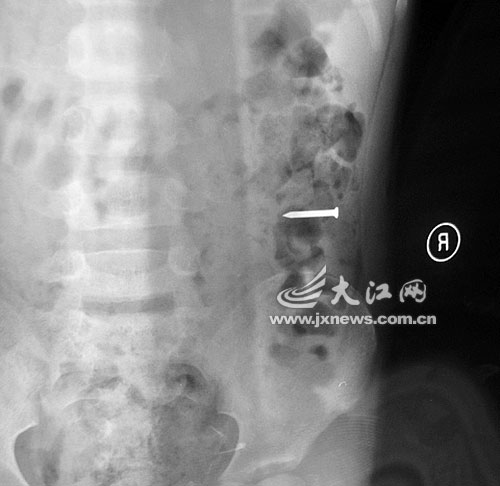

江西留守兒童吞硬幣留父母:勇勇誤吞鐵釘后的X光片

事發(fā)當(dāng)晚,勇勇的奶奶雇了一輛面包車,連夜將勇勇送往都昌縣人民醫(yī)院救治。當(dāng)晚,醫(yī)院經(jīng)過拍片發(fā)現(xiàn),2.5厘米的鐵釘滑到孩子的胃部。